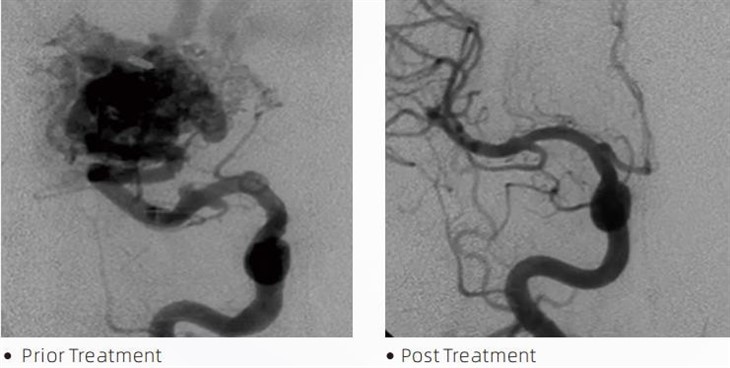

ЛаваТМемболічний клей — це медичний пристрій, який використовують інтервенційні нейрорадіологи під час мінімально інвазивних процедур для лікування таких станів, як церебральні аневризми, артеріовенозні мальформації та пухлини. Клей Lava embolic пропонує безліч переваг як для медичних працівників, так і для пацієнтів з точки зору безпеки, простоти використання та ефективності. Лава здатна швидко та ефективно закривати кровоносні судини. Процес передбачає введення клею безпосередньо в цільову судину, де він полімеризується та твердне у масу, схожу на зліпок, яка заповнює аневризму або порок розвитку. Потім він ефективно перекриває приплив крові до ураження, запобігаючи його розриву та знижуючи ризик остаточного пошкодження або інсульту. Lava включає Lava-12, Lava-18 і Lava-34. Кожен склад розроблений відповідно до конкретних клінічних потреб. Lava-18 — стандартна формула для загального використання. Lava-34 — це високов’язкий клей для ємностей із високим потоком. У той час як Lava-12 має нижчу в’язкість і більш текучий, дозволяючи дистальні мікросудини. Завдяки цим параметрам інтервенційні нейрорадіологи можуть вибрати відповідні склади Lava для забезпечення оптимальних результатів. Однією з найбільш примітних особливостей Lava є його неклейкі властивості. Ця речовина спеціально розроблена, щоб залишатися стабільною, поки не досягне цільової області. Ця характеристика означає, що емболічний клей Lava можна точно розмістити в артерії та залишатися там, не прилипаючи до навколишньої тканини.